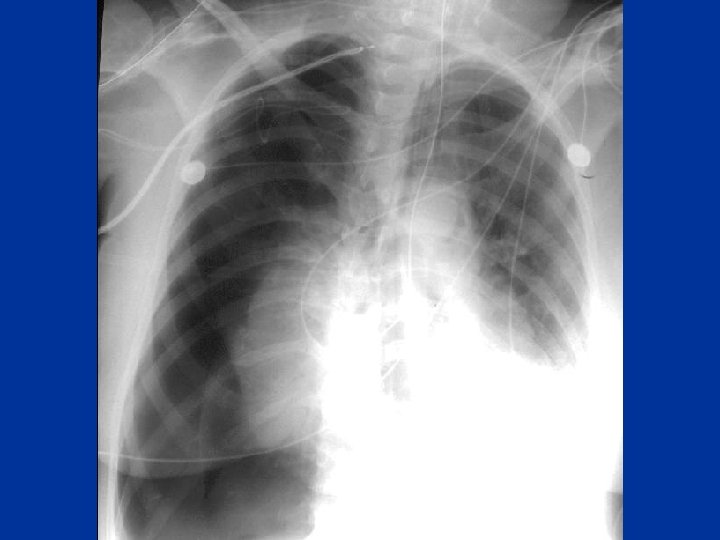

Pulmonary Embolism Risk factors: • H/O hypercoagulable • tachycardia disorder, recent DVT • Tachypnea • Surgery, immobility • Loud P 2 • cancer • Pleural effusion • Symptoms: pleuritic • Acute Cor Pulmonale Chestpain, SOB • hypotension • hymoptysis • ABG • CXR • ECG • VQ • Spiral CT • Doppler LL